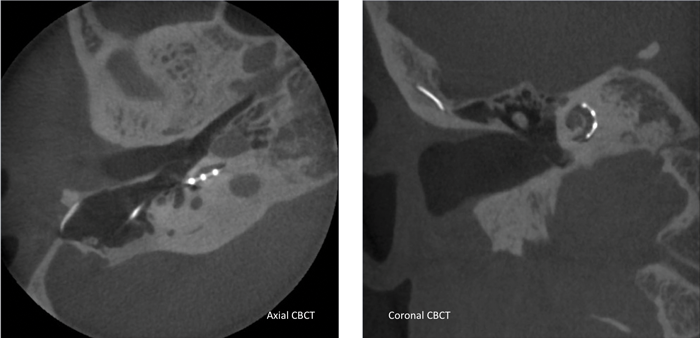

Typically after implantation a modified Stenver’s view X-ray is taken to check electrode placement. In some countries postoperative CT scans are available providing detail about scalar position and distance to the modiolus for individual electrode contacts. This level of detail has been used to guide mapping with positive outcomes for some individuals [3]. Some health systems do not permit the additional postoperative CT scans because of concerns around the added radiation dose. Cone beam CT is a potential alternative due to lower radiation dose, reduced metal artefact and enhanced detail [4] (Figure 1).

Figure 1. Left: Axial cone beam CT confirming that the array is in the scala tympani in the section shown. Right: Coronal cone beam CT showing the electrode array coursing around the lateral scalar wall.